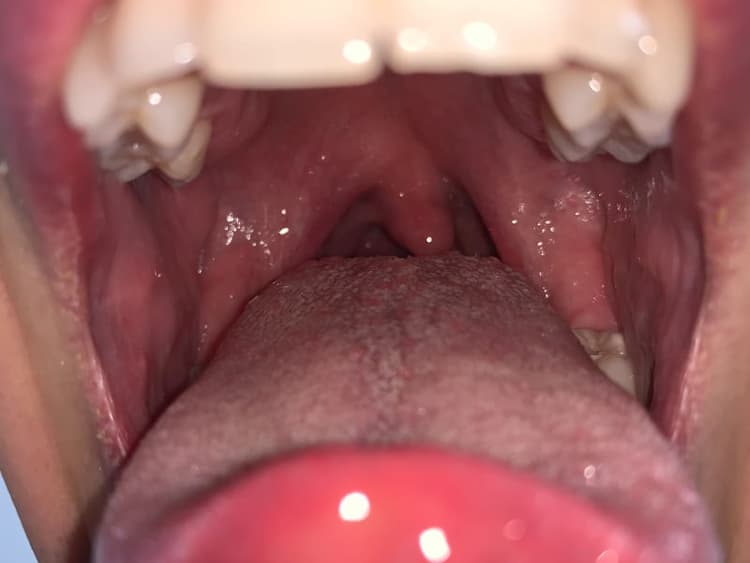

Tonsillitis Symptoms (Plus Treatment) Definitive Guide

Tonsillitis Push Or Abcess Infection On Throat Induce Pain And Fever Can You Have A Chest Infection And Tonsillitis At The Same Time Signs and symptoms of tonsillitis include swollen. Here’s what you need to know about tonsillitis, from its symptoms to treatments that can help. Sometimes the infection can spread from the tonsils to other nearby tissues. Some chest infections are mild and clear up on their own, but others can be severe. The tonsils are your first line of. Tonsillitis is. Can You Have A Chest Infection And Tonsillitis At The Same Time.